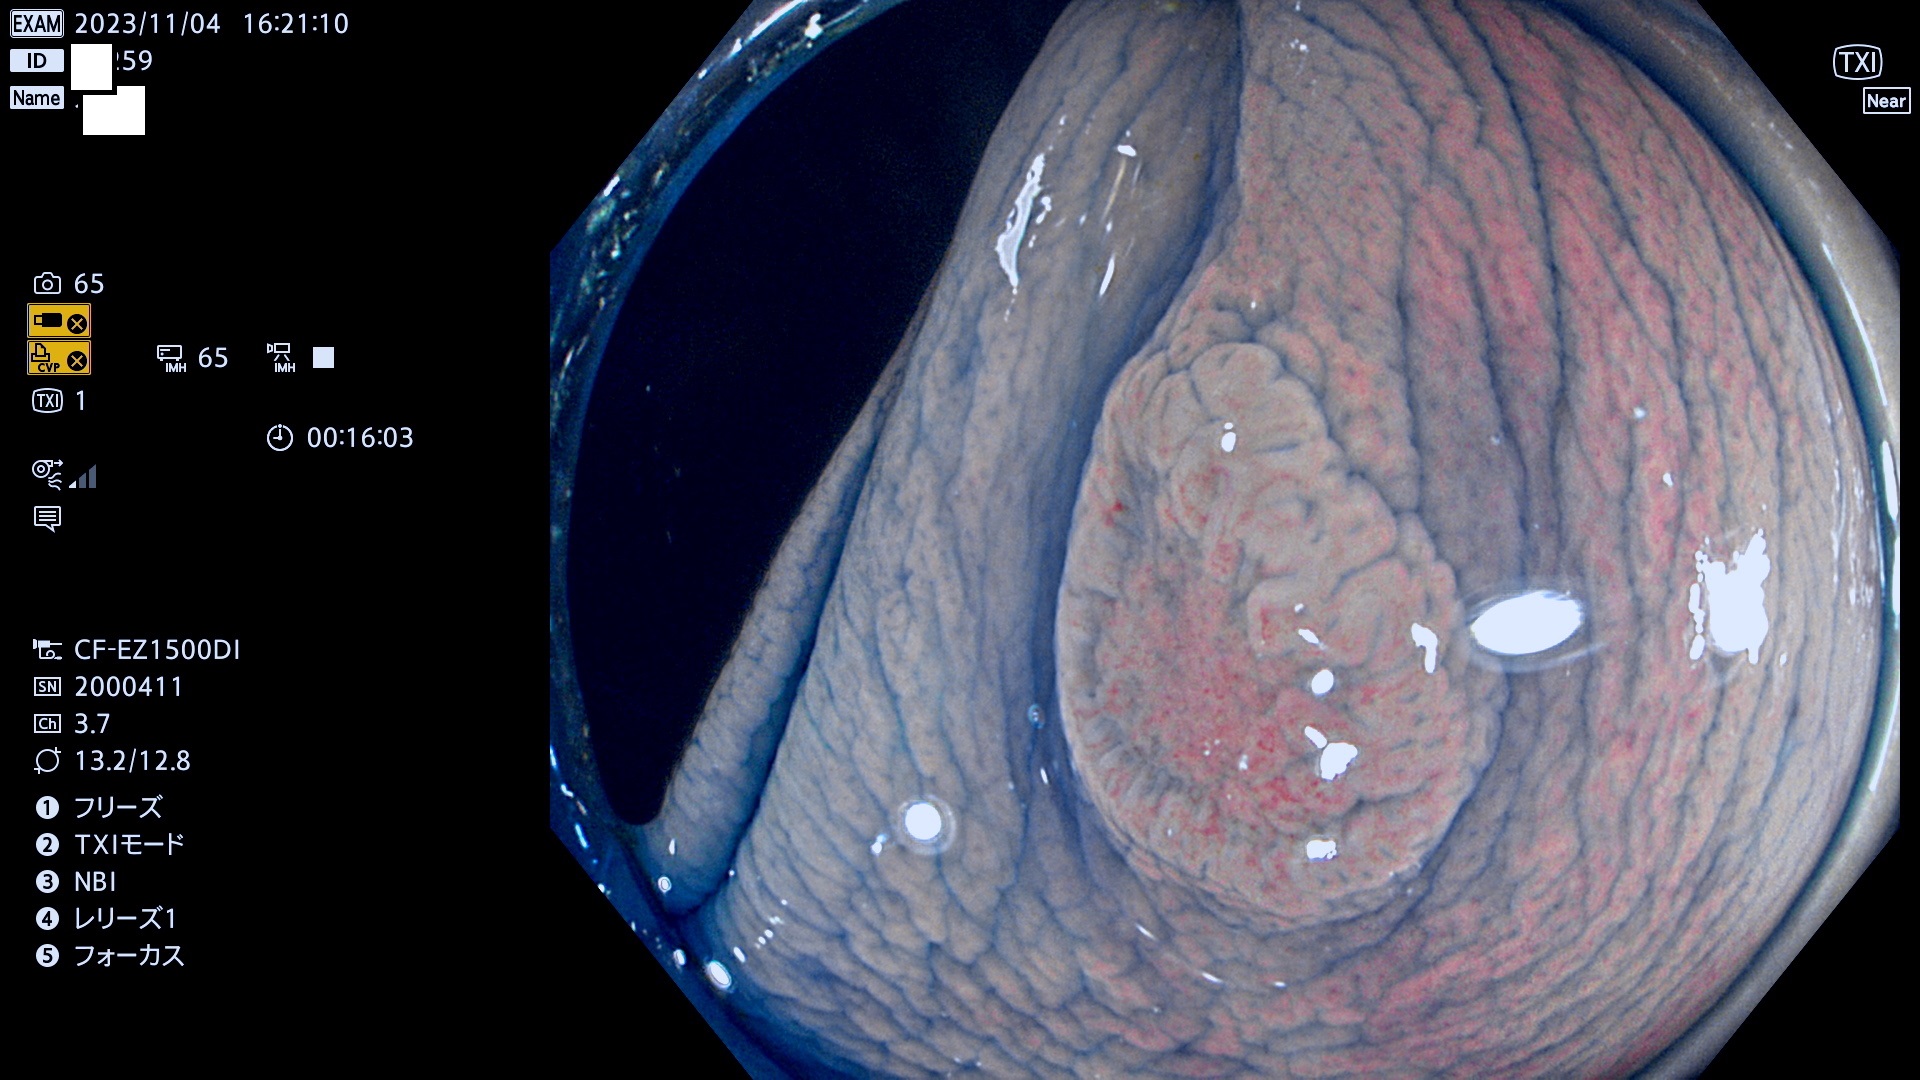

表面型腺腫(Flat Adenoma)の中で、完全に平坦な物をUb、陥凹している物をUcと呼びます。平坦隆起型(Ua)よりも、発見が難しく危険な病変です。このタイプは「内視鏡後・大腸癌の重要犯人」であり、この発見率は「腺腫発見率」よりも、重要な意味があります。

専門的)何故、陥凹していると危険? 癌遺伝子の変異が蓄積すると細胞分裂が盛んになり隆起するのでは?と通常は思われるでしょう。しかし実際は逆です。これは2022年の記事にある「細胞はストレスに直面したら細胞分裂を止める(細胞老化に入り休眠する)という生命の基本的現象」によるものです(Oncogene Stress)。細胞老化を起こすのが癌抑制遺伝子で、この安全装置(ブレーキ)が壊れると癌になります(休眠からの覚醒)。ですから陥凹は「まだ癌では無いが癌化の直前」を意味します。特に「小サイズなのに陥凹している」病変は短期間に腫瘍進化(⇒2021年記事)が起きたことを意味します(=ゲノム不安定性

毎週の検査(木・金・土・日)に発見されたUb、Uc型・腺腫を、その週の日曜の夜にUPし1週間、提示します。

抽出の対象期間 2023年11月2日(木)〜11月6(月)の5日間(60件の検査)11件